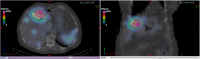

(A) Anatomic segmentation (for whole liver and kidneys). (B) Functional segmentation for lesions. (C) Normal liver from Boolean subtraction.